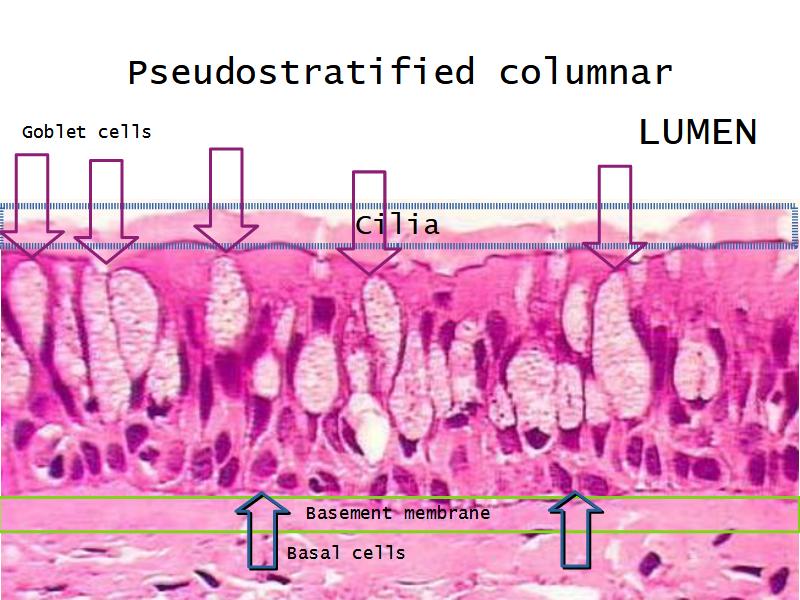

Respiratory epithelium

- Pseudostratified

- Ciliated

- Columnar

- Epithelium with

- 4 Cells

- Ciliated columnar cells

- Non-ciliated columnar cells

- Goblet cells

- Basal cells